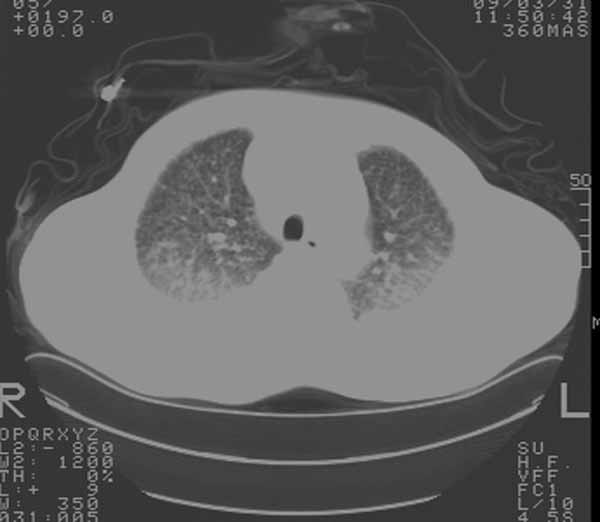

以下是引用余辉在2009-3-31 18:43:00的发言:[br]肺水肿,双侧心腔积液,心包积液,心影增大,疑似心衰

以下是引用wangyong1977在2009-3-31 20:46:00的发言:[br]肺水肿,双侧胸腔积液,心包积液,心影增大,疑似心衰 [br]

以下是引用宇宙ct在2009-3-31 18:57:00的发言:[br]肺水肿,双侧心腔积液,心包积液,心影增大,疑似心衰 [br] [br]